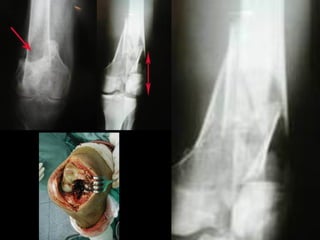

Patologias envolvendo fraturas,

corpos estranhos ou lesões ósseas.

Fratura do platô articular Fratura de calcâneo

Fratura dos Maléolos